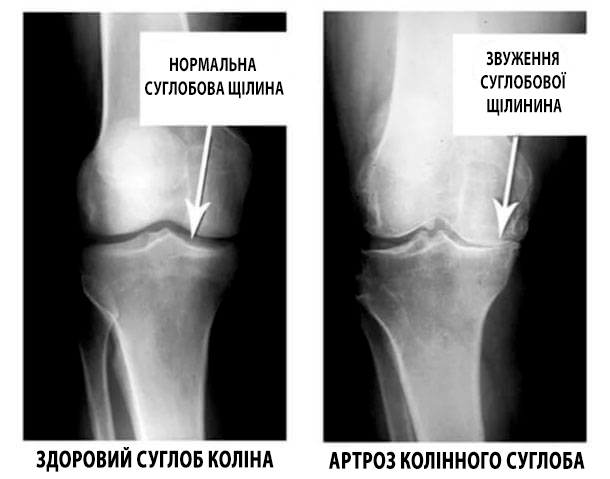

Погляньте на ці знімки, ви бачите, що на правому знімку суглобова щілина відсутня, кістки труться один об одного, викликаючи сильний біль. І цей процес дуже важко зупинити! Через пару років людина стане інвалідом і не зможе себе обслуговувати.

А. Конзюба : Насамперед, це травми та серйозні навантаження. Зайву вагу також надає сильний тиск на суглоби. Малорухливий спосіб життя, стреси, велика кількість солі і цукру в їжі все це розм'якшує хрящову тканину, зношує та стоншує її. Від кожного нового руху хрящ стирається і деформується, кістки починають тертися один об одного, викликаючи нестерпну біль.